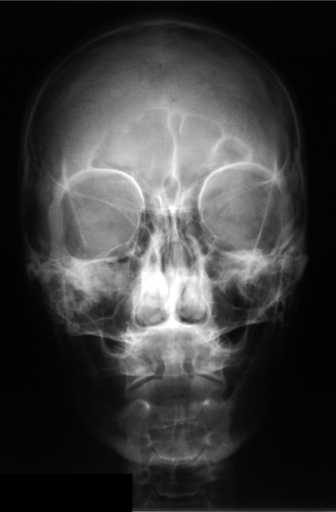

Figure 2 shows barcode annotations for two medical images from IRMA dataset [34, 35] for different values (see lines 4 and 10 in Algorithm 1). Hence, the algorithm works with equidistant angles of projection.

In this section, we report two series of experiments. The first one verifies the correctness or reliability of the micro-DE algorithm to find optimal projections compared to an exhaustive search when we are looking for 4 optimal projection angles out of 16 equidistant angles. In the second experiments, we still provide the results for exhaustive 4/16 selection but examine the evolutionary approach to get 4/180 and 8/180 to investigate the reconstruction accuracy of the micro-DE via correlation of the input image and the reconstructed image using 4/16 (exhaustive), 4/180 (micro-DE) and 8/180 (micro-DE). To conduct the experiments we used 50 images from IRMA dataset [34, 35], a benchmarking collection of 14,400 x-rays images. We selected 10 random classes out of 58 classes, and for each class, we randomly drew 5 images to be used in our experiments. Figure 4 shows the images we have used.